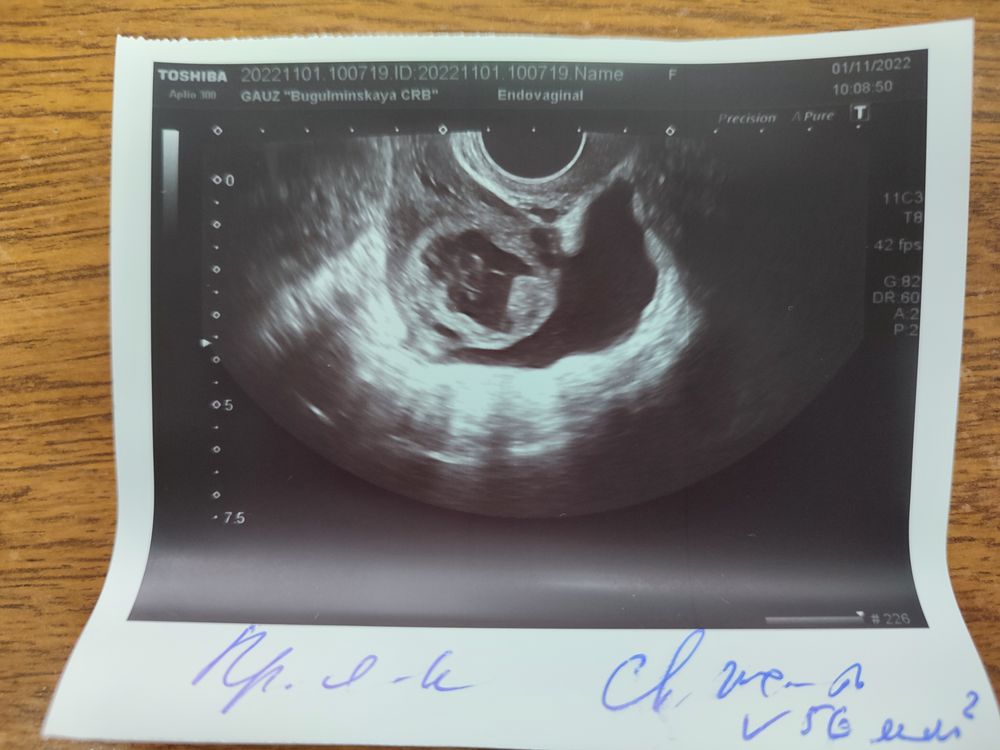

Была сегодня на УЗИ 20 дц

М эхо 12 мм

В правом яичнике узистка увидела максимальный фолликул 28 мм с неровными контурами, но как???Ведь овуляция уже была

Свободная жидкость 56 мл, никогда такого кол-ва жидкости не было!

На фото киста желтого тела. Жидкость после овуляции. Количество ее не имеет значение. Столько вылилось значит при овуляции.